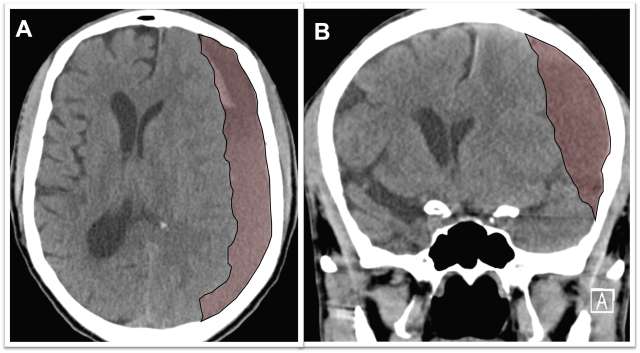

Figure 1

Figure 1. A) Axial view of a brain CT scan demonstrating a chronic subdural hematoma collection below the skull (the skull is bright white) shifting the brain (brain surface is marked with the yellow line) to the other side. B) Coronal view of the same patient demonstrating the chronic subdural hematoma occupying the subdural space and shifting the brain to the other side (brain surface marked with yellow line).